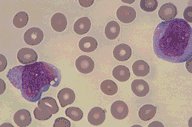

M7 - Acute Megakaryocytic, PB

ANLL M7: Wright's stained peripheral blood

smear showing two immature leukemic

megakaryoblasts. Other studies were required to

confirm their identity.